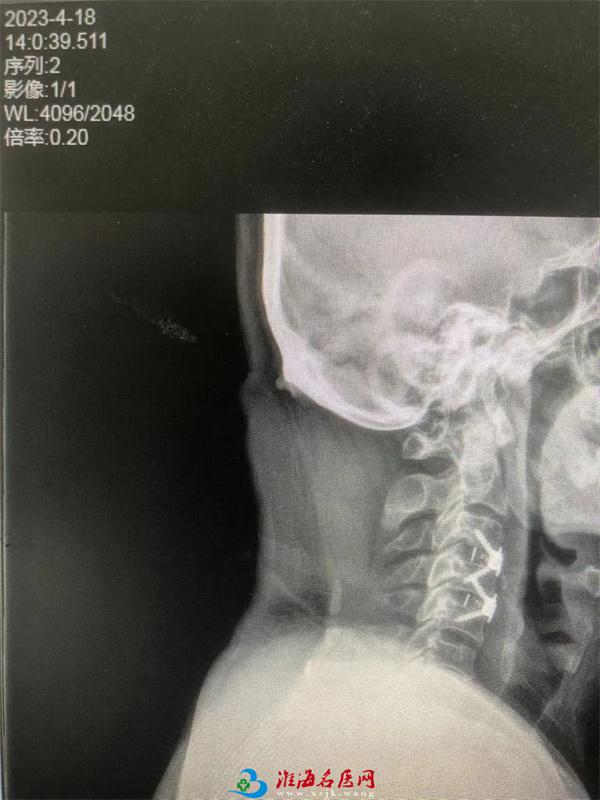

这不,患者韦某,因右肩部疼痛半年伴双手指及双足趾麻木4月余来院治疗,骨科接诊医生陈建伟经过仔细询问病史,细致查体及进行CT和核磁共振检查阅片后,判断患者为颈椎后纵韧带骨化、颈椎间盘突症,骨科主任刘伟带领治疗团队,根据患者病情科内进行讨论后决定为其进行手术治疗,为了减轻对颈部椎体前缘软组织器官损伤及保护食道、缩短手术时间,决定放弃传统椎间融合加钢板手术方式,采用“零切迹”椎间融合手术方式,并针对此手术制定了个性化诊疗方案。经过周密术前准备,在刘伟主任、陈建伟主治医师、麻醉师、手术护士的密切配合下,患者手术顺利完成。术后第二天饮食正常,无吞咽困难,因脊髓压迫的肢体麻木症状得到明显改善,术后第三天就下床活动了。

手术前

手术后